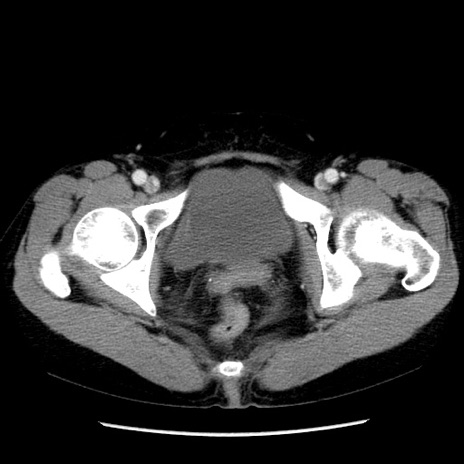

症例6(横断像)

【症例】50歳代女性

【主訴】下腹部痛

【現病歴】本日朝より下痢2回あり。 昼食を食べた後、嘔吐3回、下腹部痛認め、症状軽快せず、当院救急搬送。

最終食事:本日昼(生ものなし)。 昨日の夜、刺身を食ぺたとのこと。周囲に同様の症状の者なし。普段、排便は毎日あるとのこと。

【既往歴】卵巣癌術後(8年前に当院で卵巣摘出)

【身体所見】 意識清明、腹部:平坦、腸蠕動音→、やや硬、下腹部自発痛・圧痛あり、反跳痛あり、筋性防御なし。

【データ】WBC 16000、CRP 0.01